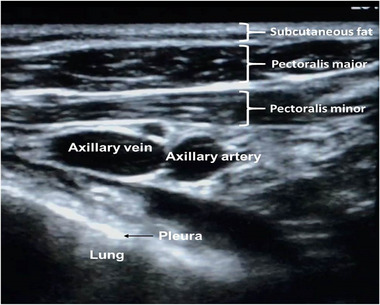

Background: There is limited real-world experience of the learning curve for ultrasound (US) guided axillary venous access for cardiac device implantation, and it is usually performed before cutaneous incision. We investigated the learning curve, radiation exposure, safety, and efficacy of US-guided venous access in standard workflow.

Methods: US-guided access was performed by an experienced electrophysiologist with no prior application of the technique by using a standard vascular US probe and minimal modification to workflow. The learning curve was evaluated using access time (needle-to-wire time). Complications were recorded until hospital discharge, and efficacy was defined by procedural success. Radiation dose savings were estimated based on fluoroscopy time for access, and a control group underwent conventional fluoroscopy landmark-guided access (n = 44 punctures).